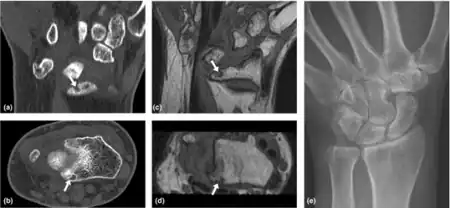

| Loss of Motion-Wrist of rheumatoid arthritis individual a-e) | |

- Loss of motion (symptom): the patient notices that the joint (or many joints) do not move as far as they used to or need to. Loss of motion is a feature of more advanced stages of arthritis including osteoarthritis, rheumatoid arthritis and ankylosing spondylitis.

- Loss of range of motion (sign): the examining medical professional notes that the range of motion of the joint is less than normal. Routine examination by an orthopaedic surgeon or rheumatologist will often pay particular attention to this. The range of motion may be measured and compared to the other side and to normal ranges. This sign is associated with the same causes as the symptom. In extreme cases when the joint does not move at all it is said to be ankylosed.